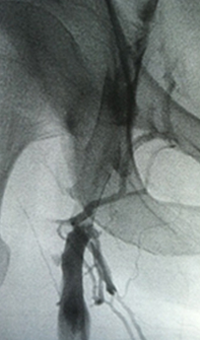

Acute DVT left lower extremity revascularization

47 year old male presented with leg swelling ~2 weeks.

Procedural steps

• Power Pulse delivery of 10mg tPA followed by

• 20 minute dwell time

• Total runtime was 300 seconds

Acute DVT Left Lower Extremity Revascularization pre-treatment angio.

Acute Iliofemoral thrombus pre-treatment

IVC Filter placed (left image)

Acute DVT Left Lower Extremity Revascularization post-treatment.

Post ZelanteDVT  pharmacomechanical thrombectomy

Case images courtesy of David Wilson M.D. – Harbin Clinic, Rome, Georgia – December 19, 2015